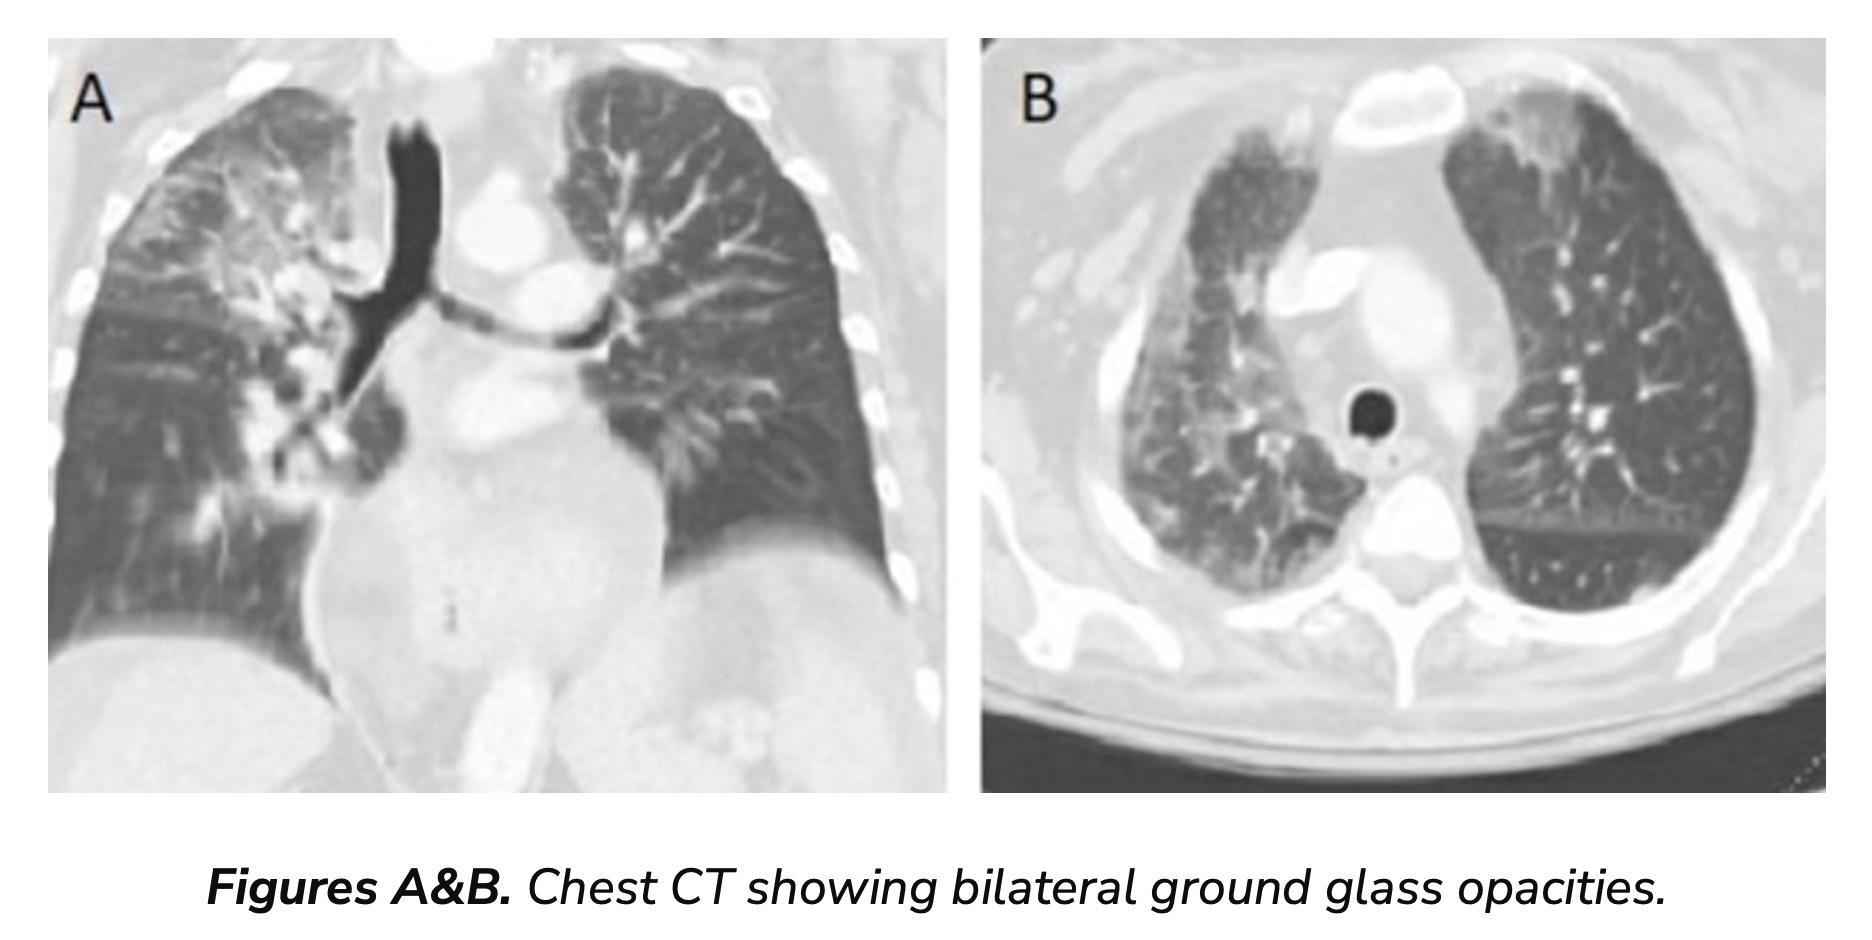

We had a tragic case highlighting this critical need to prioritize PJP prophylaxis in AAH. The patient, an adult over the age of 60, was initially managed for severe AAH with high-dose steroids and later was admitted following a fall and rapid clinical deterioration. This patient developed acute hypoxic respiratory failure requiring mechanical ventilation. The chest imaging was consistent with bilateral diffuse opacities in the lung fields. (Figures A&B) No overt cause of respiratory failure was determined. Infectious workup was unrevealing for bacterial causes while the patient remained on broad-spectrum antibiotics. Due to refractory hypoxemia and multi-organ failure with shock, the patient was transitioned to comfort care. Two days after the patient died, the bronchial alveolar lavage revealed a positive PCR for PJP. Unfortunately, it was too late for any meaningful intervention.